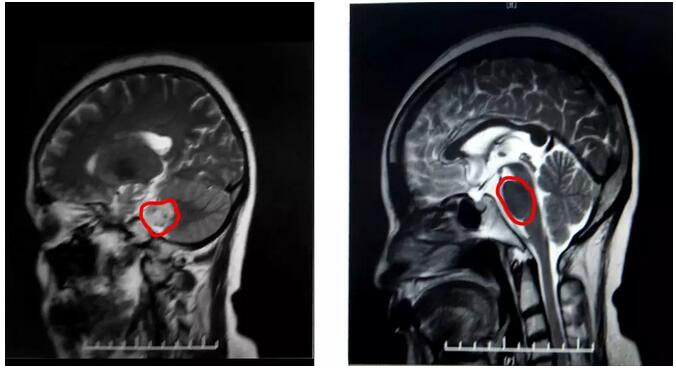

不查不知道,一查吓一跳!吕阿姨被确诊患有右侧听神经瘤。听神经瘤虽然是一种良性肿瘤,但若不进行手术切除,会像气球一样逐渐膨胀,最终压到周围的神经和血管,导致患者出现耳鸣、听力下降、突发性耳聋、共济失调、语言不清和发音困难等症状。病情严重者,甚至可能发生脑疝,危及生命。

据磁共振影像显示,吕阿姨的肿瘤位于内听道与中脑、小脑交界处,还很可能与面神经粘连程度严重,而由于肿瘤巨大,听神经、面神经大多受压变得菲薄,术中辨认困难,术后难以保留功能;同时术中处理不当还易影响小脑、脑干等功能;这些困难无疑都决定了这将是一台较高难度的手术。

▲ 术后CT显示肿瘤基本已被切除